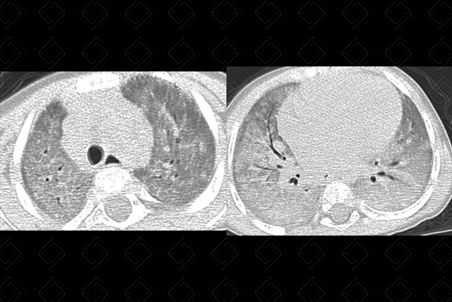

Texto alternativo para a imagem Figura 1. Créditos: Dra. Elazir Mota - Rio de Janeiro/RJ

Descrição da figura 1: Radiografia de tórax, paciente sexo masculino, 3 anos, evidenciando extensas opacidades reticulares dispersas pelo parênquima pulmonar.

• Radiografia de tórax: Presença de consolidações parenquimatosas difusas e bilaterais ou opacidades mal definidas bilaterais (devendo representar as opacidades em vidro fosco melhor caracterizadas na TC) (figura 1);